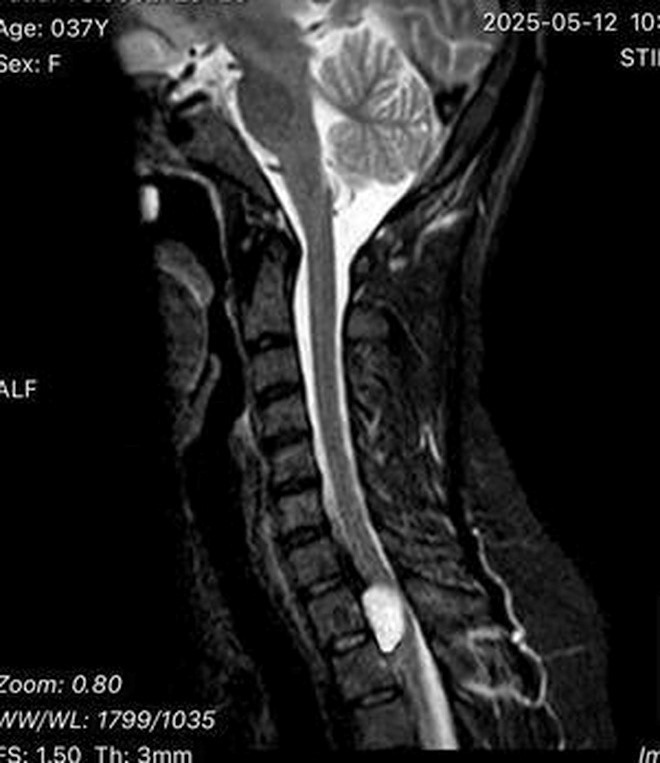

Tuy nhiên, sau vài tuần, tình trạng tê bì tiến triển kèm theo cảm giác yếu tay, tức ngực, khó thở. Khi đến khám tại Bệnh viện Hữu nghị Đa khoa tỉnh Nghệ An, kết quả chụp cộng hưởng từ (MRI) cho thấy bệnh nhân có khối u nằm trong ống sống ở vị trí ngực cao (D1–D2), chiếm trọn ¾ tủy sống. Phần còn lại của khối u chui qua lỗ liên hợp đi ra ngoài, xâm lấn vào đỉnh phổi.

Chính vì vậy, y học gọi khối u này là u hình quả tạ (dumbbell tumor) vì có hai phần: một phần nằm trong tủy sống, một phần xâm lấn vào vùng đỉnh phổi. Tỷ lệ gặp loại u này rất thấp, chỉ khoảng 0,3–0,4 trường hợp trên 100.000 người.

Kết quả chụp cộng hưởng từ (MRI) có khối u nằm trong ống sống ở vị trí ngực cao (D1-D2) xâm lấn chiếm trọn ¾ tuỷ sống.